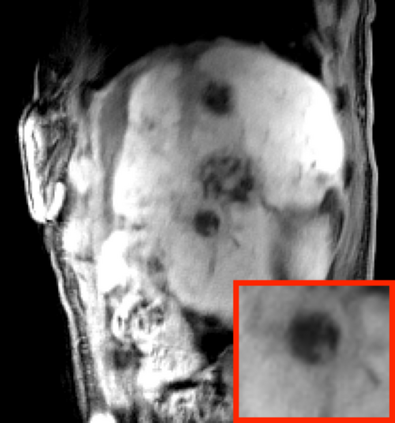

Deep neural networks for medical image reconstruction are traditionally trained using high-quality ground-truth images as training targets. Recent work onNoise2Noise (N2N) has shown the potential of using multiple noisy measurements of the same object as an alternative to having a ground truth. However, existing N2N-based methods cannot exploit information from various motion states, limiting their ability to learn on moving objects. This paper addresses this issue by proposing a novel motion-compensated deep image reconstruction (MoDIR) method that can use information from several unregistered and noisy measurements for training. MoDIR deals with object motion by including a deep registration module jointly trained with the deep reconstruction network without any ground-truth supervision. We validate MoDIR on both simulated and experimentally collected magnetic resonance imaging (MRI) data and show that it significantly improves imaging quality.